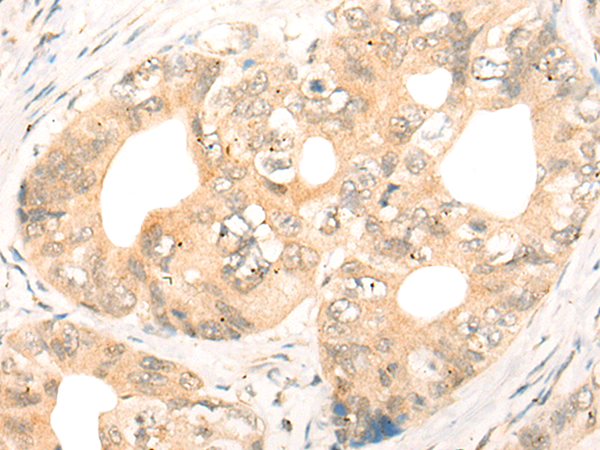

IHC positive control: |

Human gastric cancer |

IHC Recommend dilution: |

40-200 |